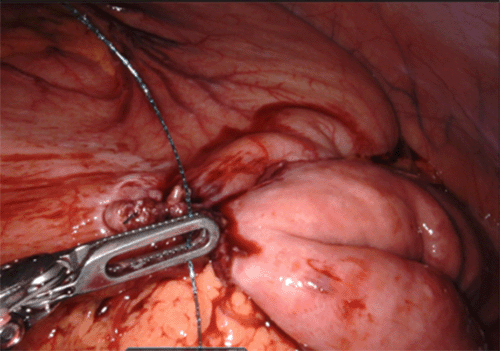

Insufflation was set to 14 mmHg. The patient was then placed in a 20-degree reverse Trendelenburg, and Xi surgical robot was properly docked. We identified a chronically large, dilated stomach, a mild proximal dilation in the pyloric region, and a decompressed distal duodenum. These findings indicated the obstruction was at the D1–D2 intersection, and the patient would not require a Strong's procedure, only a gastrojejunostomy. After clearly identifying the obstruction, we isolated a loop of jejunum 25 cm distal to the ligament of Treitz. The small bowel loop was then brought up in an antecolic fashion to the most dependent portion of the greater curvature of the stomach. A 3-0 Vicryl was used to secure the antimesenteric portion of the small bowel to the anterior dependent portion along the greater curvature of the stomach with two interrupted stitches. After creating a gastrotomy and enterotomy, the robotic GIA 45 stapler with blue load was used to create a side-to-side functional gastrojejunostomy (Figure 6).

Figure 6. Robotic GIA 45 Stapler Using Blue Load Advanced into Stomach and Jejunal Limb to Create Gastrojejunostomy. Published with Permission

The terminal defect was closed with a running 3-0 absorbable V-loc suture maintaining bowel patency throughout (Figure 7).